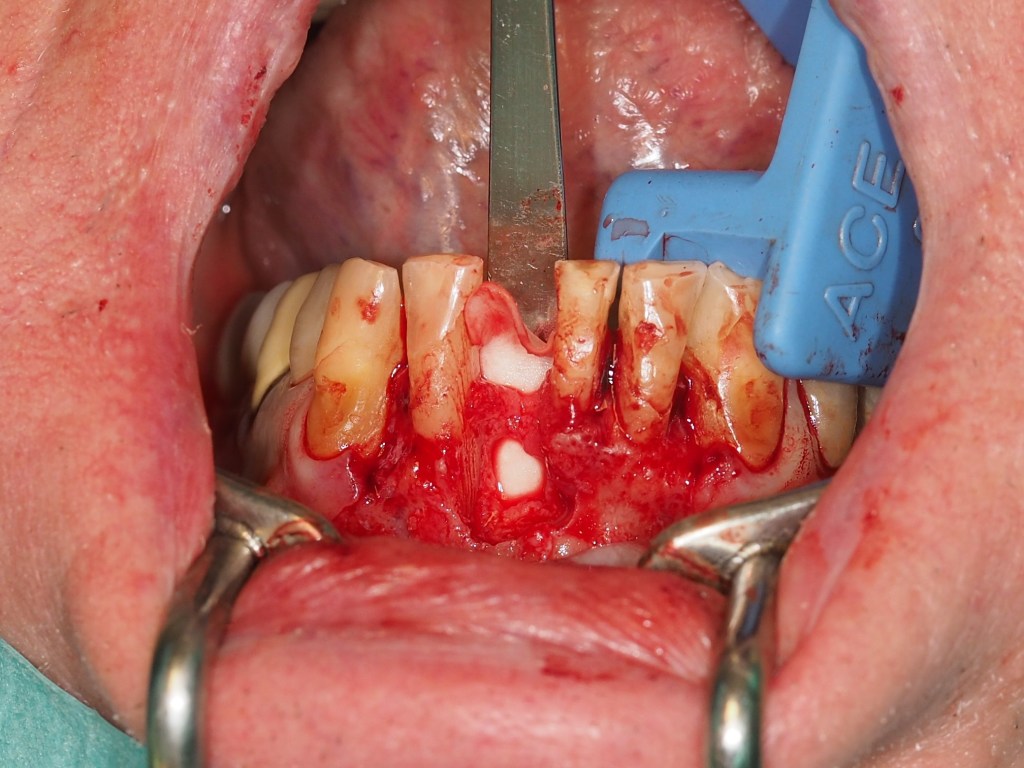

Se decide la extracción del diente 4.1 y la realización de una regeneración ósea guiada mediante el uso de hueso autólogo y membranas reabsorbibles en silla de montar. El diente 3.1 se mantiene de forma estratégica como soporte para una restauración provisional, anticipando su futura extracción en la fase final del tratamiento. En las fotos intraorales de la cirugía, tras la extracción el incisivo y legrado del granuloma, podemos apreciar la ausencia de hueso por vestibular y una perforación en la cortical lingual. (Figuras 9-12).